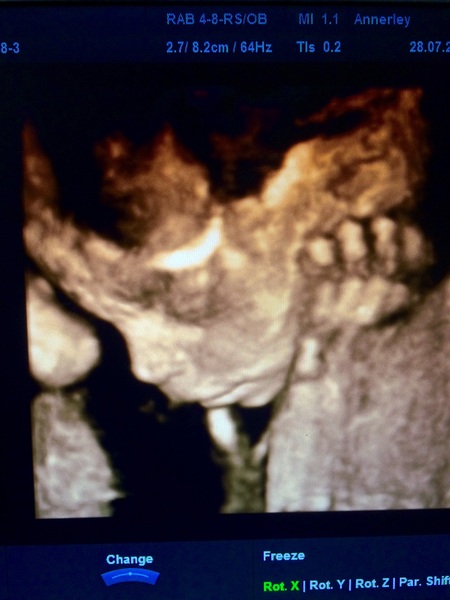

Hi all. Hope you don't mind but I'm so excited about my scan picture today I really wanted to share it. Here's my DD!